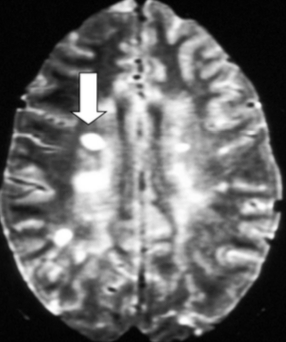

What do you see here?

What is one of the typical distributions of MS plaques?

In addition to the classic periventricular plaques, where else in the brain can these be in MS pts?